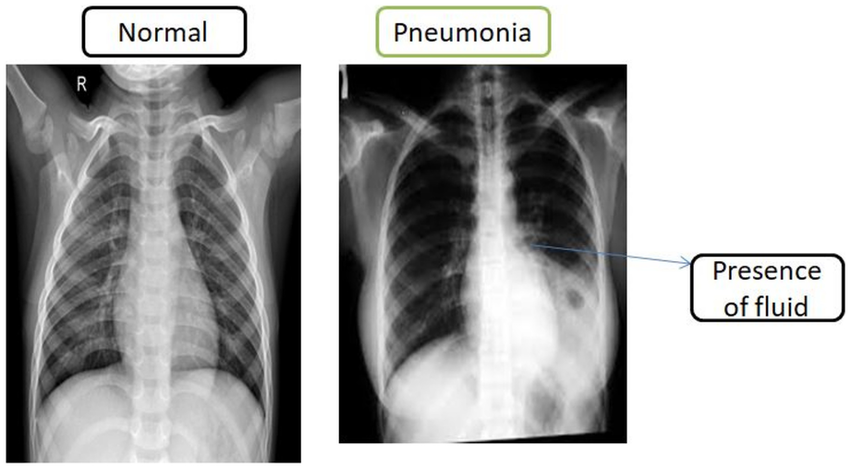

- Physical Exam: A doctor listens to the lungs with a stethoscope for crackling or rattling sounds (rales) and assesses breathing patterns.

- Chest X-ray: Confirms pneumonia by showing areas of lung inflammation or consolidation.